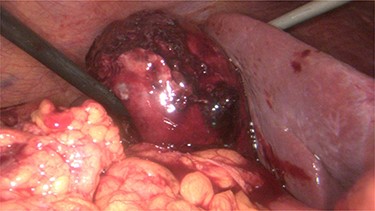

A 68-year-old male with arterial hypertension, dyslipidemia, cerebrovascular disease and a history of coronary heart disease, who had already done several percutaneous coronary interventions with stent placement, went to the emergency department with precordial pain and vomiting. At admission, he had an electrocardiogram in sinus rhythm with negative T waves V4–V6, DI and aVL. His blood test revealed leukocytosis 13 790/l with neutrophilia 11 600/l and polymerase chain reaction (PCR) 0.05 mg/dl, with normal cardiac markers. The pain improved with sublingual nitroglycerin. He was admitted and, on the next day, underwent a coronary angiography with angioplasty on the second diagonal of the anterior descending artery with stent placement due to a 70–90% lesion. During the procedure, he performed 5000 Units of heparin and 1 mg of isosorbide dinitrate. After the procedure, he was obnubilated and hypotensive, which improved with fluid challenge. New blood test was taken with evidence of increased leukocytosis to 17.540/l, PCR to 16.4 mg/dl, total bilirubin to 1.52 mg/dl, direct bilirubin 0.74 mg/dl, with normal aminotransferases and gamma-glutamyl transferase. Blood cultures, urine culture, chest X-rays were performed, and empiric antibiotics were started with piperacillin/tazobactam, and the consultation of general surgery was requested. In the evaluation it stands out that the patient was hypocoagulated and with dual antiplatelet therapy, with abdominal pain and defense in the upper quadrants. In blood test he had a slight increase in the international normalized ratio (INR) of 1.26 and in the prothrombin time. An abdominal ultrasound and CT scan (Fig. 1) was performed with evidence of gallbladder hydrops, with high-density contents suspected of thick mud, or hematic content, with a thickened gallbladder wall (~ 4–5 mm), with perivesicular fluid and perivesicular fat densification favoring the hypothesis of acute cholecystitis (Fig. 1). In this context, the patient underwent laparoscopic cholecystectomy on the same day with intraoperative diagnosis of acute gangrenous cholecystitis with intravesicular hematoma and hemoperitoneum (~450 cc) (Fig. 2 and video 1).

In the postoperative period, the patient evolved well, ending up being discharged on the ninth day of hospitalization. The gallbladder histology showed intense congestion and extensive hemorrhagic areas compatible with lesions of acute purulent hemorrhagic cholecystitis.